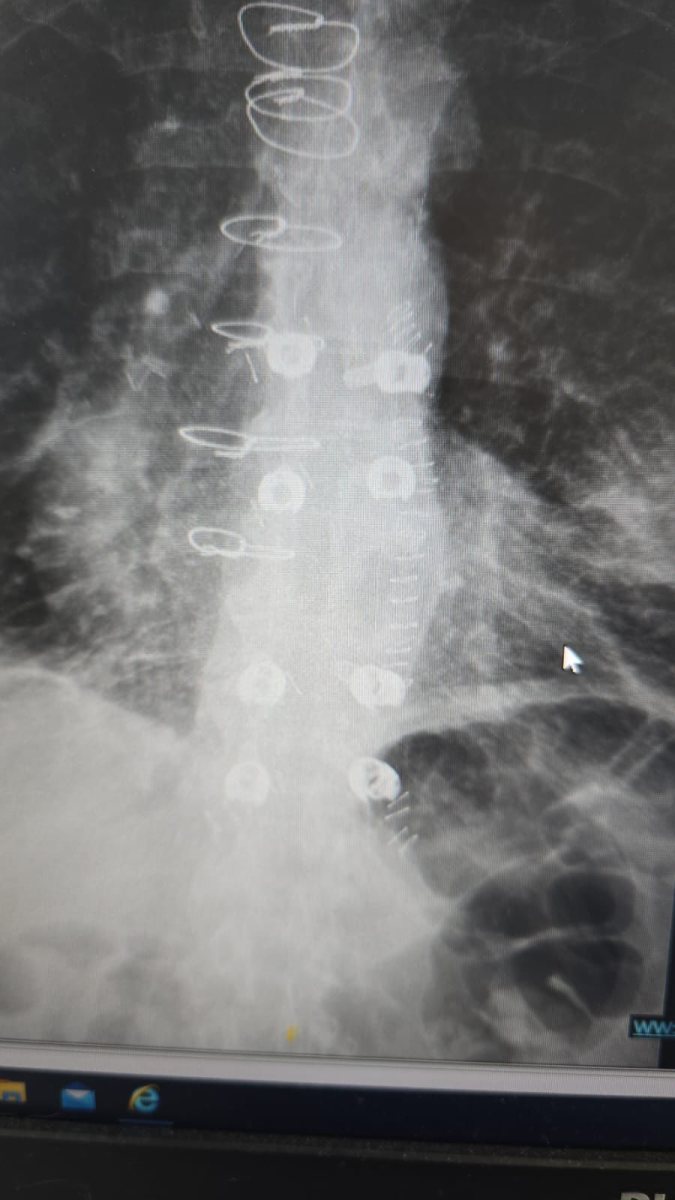

ניתוח ראשון מסוגו בעולם בוצע השבוע בבית החולים אסותא אשדוד: קיבוע עמוד שדרה זעיר-פולשני באמצעות ברגים ומוטות מקרבון, פיתוח ישראלי של חברת CarboFix.

המטופל, גבר בן 60 הלוקה בסרטן ריאה שפיתח גרורה בעמוד השדרה, הגיע למיון בסכנת שיתוק מיידית. במהלך הניתוח הוחדרו 8 ברגים ומוטות מקרבון דרך חתכים של כסנטימטר בלבד, ובמקביל הוסר הגידול שלחץ על חוט השדרה.

הטכניקה להכנסת ברגים בעמוד השדרה דרך חתכים זעירים קיימת כ-30 שנה ומשמשת בעיקר לטיפול בשברים. אולם עד כה לא ניתן היה להשתמש בחומר קרבון בשיטה זו בגלל מאפייניו הפיזיקליים המורכבים. חברת CarboFix הישראלית פיתחה פתרון שמאפשר את השילוב.

שתלי הקרבון אינם יוצרים הפרעות בהדמיות MRI ומפחיתים סיכונים בהקרנות, ומאפשרים לרופאים לכוון את הקרינה בדיוק רב יותר לאזור הגידול.